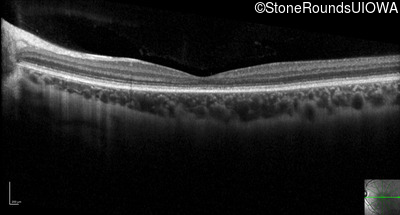

Optical Coherence Tomography - Right - 20/32

Exemplar / OCT Stack